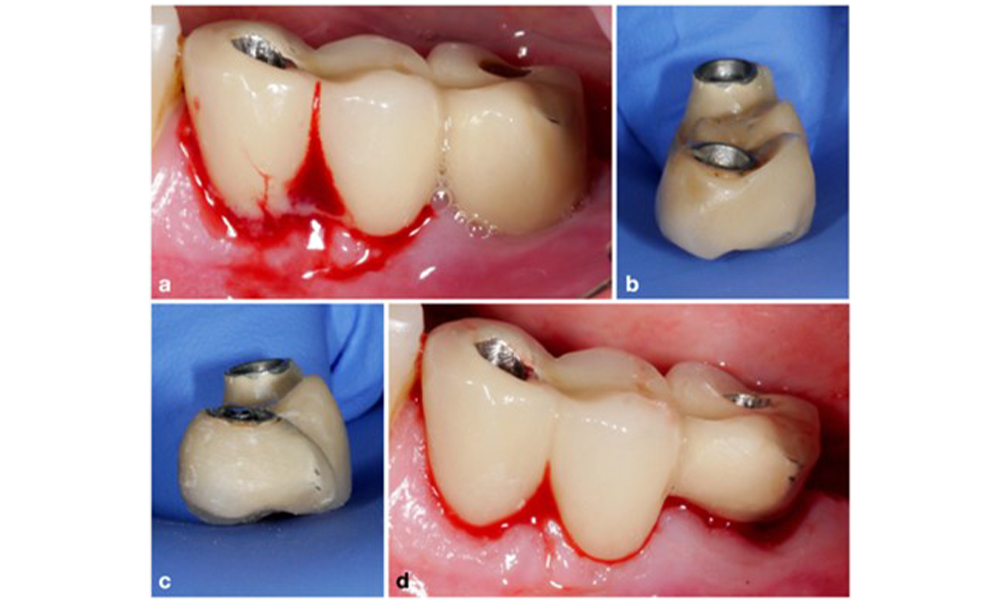

Auf dem World Workshop on the Classification of Periodontal and Peri‐Implant Diseases and Conditions 2017 wurden diagnostische Kriterien für periimplantäre Mukositis und Periimplantitis festgelegt (Renvert et al. 2018). Periimplantäre Mukositis ist definiert als (1) Entzündung um das Implantat (also Rötungen, Schwellungen, Blutfäden oder Blutstropfen innerhalb von 30 Sekunden nach dem Sondieren), jedoch (2) ohne zusätzlichen Knochenverlust nach der Ersteinheilung (Abb. 1).

Periimplantitis ist zu erkennen an (1) Entzündungszeichen, vergleichbar einer Mukositis, (2) einem radiologischen Nachweis von Knochenverlust nach Ersteinheilung und (3) der Zunahme der Sondierungstiefe im Vergleich zu Messungen kurz nach dem Einsetzen der prothetischen Rekonstruktion (Abb. 2). Liegen keine früheren Röntgenaufnahmen vor, weisen ein radiologisches Knochenniveau von ≥ 3 mm zusammen mit Sondierungsblutungen und Sondierungstiefen von ≥ 6 mm auf eine Periimplantitis hin.